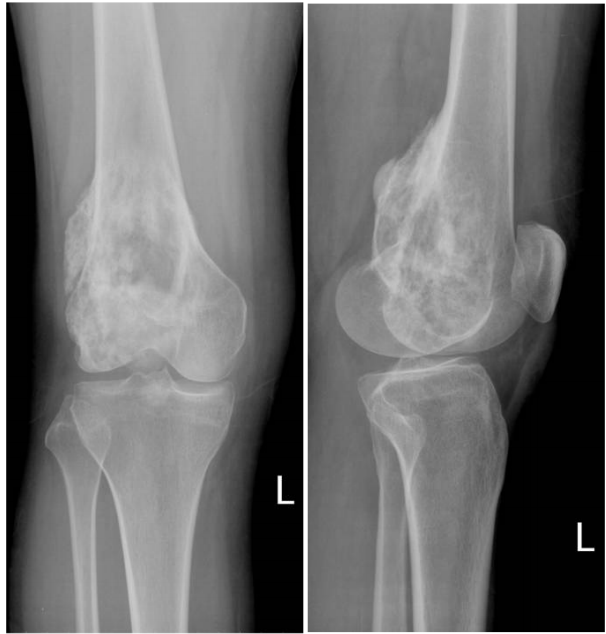

56.一位22歲女性抱怨左膝疼痛3個月,問診時發現夜間疼痛加劇。身體檢查發現明顯局部壓痛,觸診時發現有組 織腫塊。膝部X光片如下,此病患最有可能的診斷為: (A)單純性骨囊腫(simple bone cyst) (B)骨肉瘤(osteosarcoma) (C)纖維性發育不全(fibrous dysplasia) (D)骨軟骨瘤(osteochondroma)